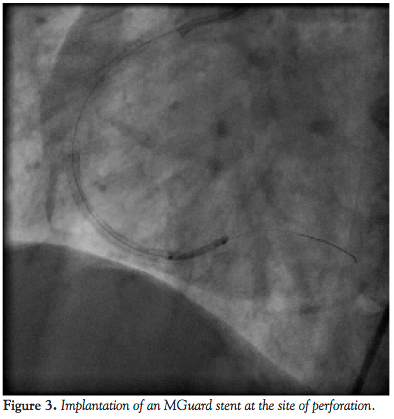

reasonable to assume that the perforation occurred near the distal stent edge as a consequence of the high-pressure predilatation. To seal the perforation, the above-mentioned net wrapped stent, a 2.5 mm x 15 mm MGuard was introduced in the territory of crux cordis. The stent was positioned to cover the distal edge of the previously implanted Endeavor stent and the perforated posterolateral branch as well, and then it was deployed at nominal pressure (Figure 3). The overlapping part of the stent was postdilated with the aid of the stent balloon at 17 atm. The implantation of the MGuard stent resulted in successful sealing of the perforation and the contrast agent extravasation was abolished. The original restenotic lesion and the de novo mid segment lesion were managed by deploying 2 Xience Prime LL 3 mm x 33 mm stents (Abbott Vascular) at 20 atm (Figures 4 and 5). No signs of hemodynamic instability appeared. After the intervention, echocardiogram revealed only 6-7 mm pericardial fluid localized at the left ventricular posterior wall. There were no significant ECG changes and the maximum CPK level was 260 U/L (upper limit of normal is 170 U/l). The patient remained stable during the following hospital stay. She was discharged on a daily dose of aspirin 300 mg and clopidogrel 150 mg. At 6-month follow-up neither angina pectoris, nor sign of coronary ischemia were revealed.